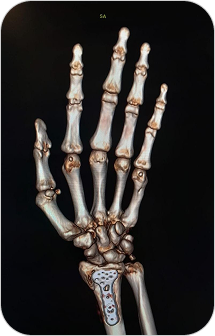

Reconstrucción 3D en Tomografía

Es una técnica avanzada que permite convertir las imágenes obtenidas por tomografía computada en modelos tridimensionales. Estas reconstrucciones permiten visualizar estructuras anatómicas de forma realista, facilitando diagnósticos más precisos y una mejor planificación quirúrgica o terapéutica.

Las reconstrucciones tridimensionales a partir de tomografía computada permiten visualizar la anatomía de forma realista y precisa, facilitando diagnósticos y cirugías complejas.

¿PARA QUE SE UTILIZA?

- Evaluación detallada de fracturas complejas, articulaciones y columna vertebral.

- Estudio anatómico previo a cirugías (traumatológicas, maxilofaciales, cardiovasculares).

- Visualización de vasos sanguíneos, tumores o malformaciones desde distintos ángulos.

- Planificación prequirúrgica más segura y personalizada.

- Educación médica y explicación visual a pacientes.

¿POR QUÉ ES UN ESTUDIO DESTACADO?

- Imágenes más claras y comprensibles para médicos y pacientes.

Facilita una mayor precisión diagnóstica. - Permite una visión global y tridimensional de la anatomía.

- Complemento ideal para especialidades como traumatología, neurocirugía, cirugía maxilofacial y oncología.

Reconstrucción 3D en Tomografía

Es una técnica avanzada que permite convertir las imágenes obtenidas por tomografía computada en modelos tridimensionales. Estas reconstrucciones permiten visualizar estructuras anatómicas de forma realista, facilitando diagnósticos más precisos y una mejor planificación quirúrgica o terapéutica.

Las reconstrucciones tridimensionales a partir de tomografía computada permiten visualizar la anatomía de forma realista y precisa, facilitando diagnósticos y cirugías complejas.

¿PARA QUE SE UTILIZA?

- Evaluación detallada de fracturas complejas, articulaciones y columna vertebral.

- Estudio anatómico previo a cirugías (traumatológicas, maxilofaciales, cardiovasculares).

- Visualización de vasos sanguíneos, tumores o malformaciones desde distintos ángulos.

- Planificación prequirúrgica más segura y personalizada.

- Educación médica y explicación visual a pacientes.

¿POR QUÉ ES UN ESTUDIO DESTACADO?

- Imágenes más claras y comprensibles para médicos y pacientes.

Facilita una mayor precisión diagnóstica. - Permite una visión global y tridimensional de la anatomía.

- Complemento ideal para especialidades como traumatología, neurocirugía, cirugía maxilofacial y oncología.